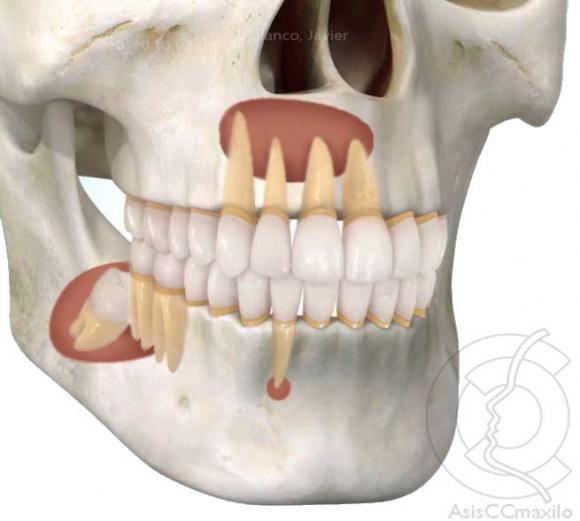

Una imagen de rayos X muestra un gran tumor en el maxilar inferior izquierdo.